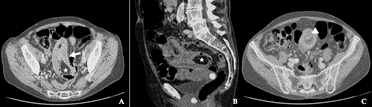

A contrast-enhanced computed tomography (CT) of the abdomen was performed, which demonstrated a suspected jejunal intussusception (target sign) due to fatty density homogenous mass measuring 5 cm that was recognized to be the lead-point of the invagination and suspected of lipoma (Figure 1). No pneumoperitoneum was detected. The patient was admitted to the surgical department, fluids were infused, and a nasogastric tube was placed. An emergency laparotomy was performed and, 30 cm distally to Treitz ligament, a jejuno-jejunal intussusception was found (Figure 2). According to benign CT findings, we conducted a partial reduction of intussusception. The presence of soft intramural palpable mass and irreversible ischaemia in a small part of the invaginated bowel, lead us to mandatory small bowel segmental resection and primary side-to-side anastomosis. Gross examination of the specimen revealed a submucosal ovalar tumor of 5 cm on the maximum axis. Histopathological analysis confirmed the diagnosis of submucosal lipoma with no signs of dysplasia or malignancy. A small bowel follow-through was ordered on day sixth: no leakage occurred, and the water-soluble contrast medium progression was regular. The postoperative recovery period was uneventful, and the patient was discharged on day nine.

Figure 1: Contrast-enhanced CT scans. Axial cut view showing A) intussusception as a sausage-shaped lesion (arrows) and C) target-shaped lesion (arrowheads). Sagittal cut view B) shows the lead point of intussusception, compatible with lipoma (star).

The classic pediatric presentation of intussusception with the typical triad of abdominal pain, a sausage-shaped palpable mass and red jelly stools is rarely seen in adults. Adult intussusception usually has a non-specific presentation: it can have an acute, subacute, or chronic onset and it is rarely considered in the differential diagnosis for abdominal complaints [3, 4, 16]. Imaging is usually required to reach a diagnosis in case of intussusception in adulthood. Plain abdominal radiographs are of limited value, due to the low sensitivity and specificity. However, they are often performed as part of initial investigations for patients presenting with an acute abdomen. One of the radiographic features consistent with intussusception is signs of intestinal obstruction proximal to the lead point [7]. On ultrasound, the classical features include the ‘target’ or ‘doughnut’ sign on transverse view and “pseudo kidney” sign on longitudinal view, but image interpretation can be difficult in presence of air. Abdominal computed tomography is the most sensitive radiological method to confirm intussusception [13, 17]. On enhanced CT scan, an intussusception due to intestinal lipoma is seen as a well-circumscribed homogeneous lesion with attenuation value between -40 and -120 UH, typical for fat [6]. The sausage-shaped lesion, pathognomonic of intussusception, is visualized when the CT beam is parallel to its longitudinal axis, whereas the characteristic target-shaped lesion is visualized when the CT beam is perpendicular [7].